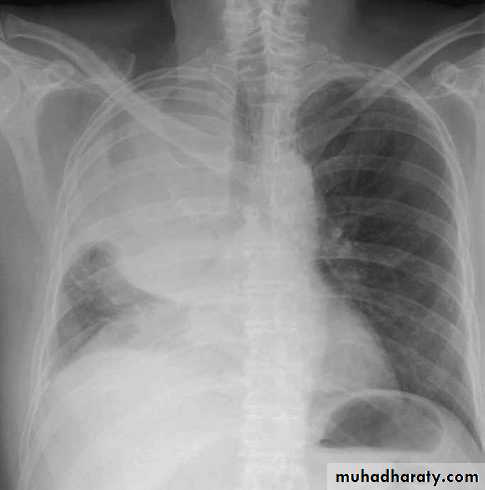

LUNG CANCER - Dr. Mustafa Nema- Baghdad College of MedicineRadiology

The most frequent finding is a mass in the lung field.Secondary manifestations seen on the CXR include lobar collapse, total lung collapse, pneumonitis because of endobronchial obstruction, elevation of the hemidiaphragm,

Elevation of the hemidiaphragm

lobar collapse & pneumonitis